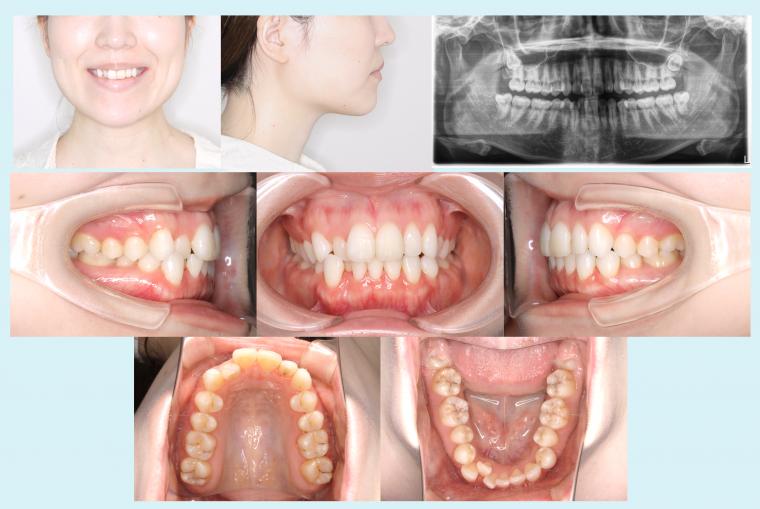

症例集の掲載をスタートいたしました。 - 2022.12.12